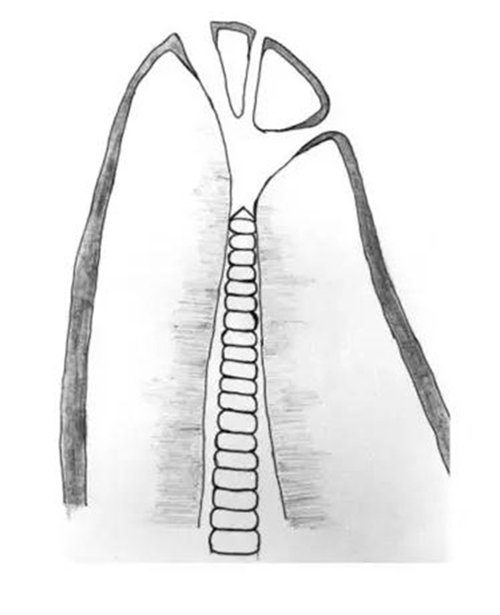

如上圖,大部分根管都逐漸往根尖向縮小,到最窄處——也就是根尖狹窄(apical constriction, AC),之后又逐漸敞開(kāi)形成根尖孔 (apical foramen, AF)。之后,Gutmann (1995) 把AC稱為根尖小孔 (minor foramen/minor diameter),AF為根尖大孔 (major foramen/greater diameter)。

A-根尖狹窄和根尖孔的圖示;B-根尖孔的臨床照片;C-組織切片展示的根尖不

根尖狹窄的分類 (Dummer et al. 1984),黑色尖頭指的是根管最狹窄處

Dummer et al. (1984) 對(duì)270個(gè)離體牙進(jìn)行縱向切割 (longitudinal sectioning) ,并在顯微鏡下觀察,發(fā)現(xiàn)傳統(tǒng)的根尖狹窄(上圖 Type A)只占46%;有30%的牙齒根管并沒(méi)有明顯最狹窄處,AC基本就在根尖開(kāi)口的位置 (Type B);19%是多個(gè)狹窄區(qū) (Type C);最后還有5%的情況是平衡的狹窄段 (Type D)。

作者還測(cè)量了由牙根尖端(apex)到根管狹窄(constriction)的距離(A-C),平均為0.89mm,基本符合臨床選擇的距影像學(xué)尖端0.5-1mm的做法,但這樣的工作長(zhǎng)度對(duì)于Type B來(lái)說(shuō)卻屬于根管欠預(yù)備(under preparation)。